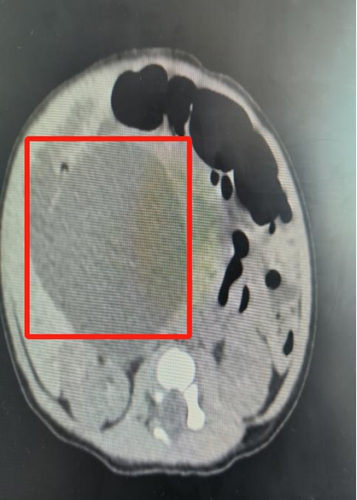

安安出生后,新生儿外科、NICU、新生儿内科、产科等科室再次进行MDT会诊,进行了全面评估,检查结果显示:胆总管囊肿,3*3cm。

△安安的囊肿迅速长到6*5cm,小小的身体里埋着一个鸡蛋大小的“炸弹”。

救治团队边控制黄疸病情,稳住肝功能,边根据预案密切观察,发现宝宝的囊肿在短时间内迅速增大,7天内从最初的3*3cm增长到6*5cm。